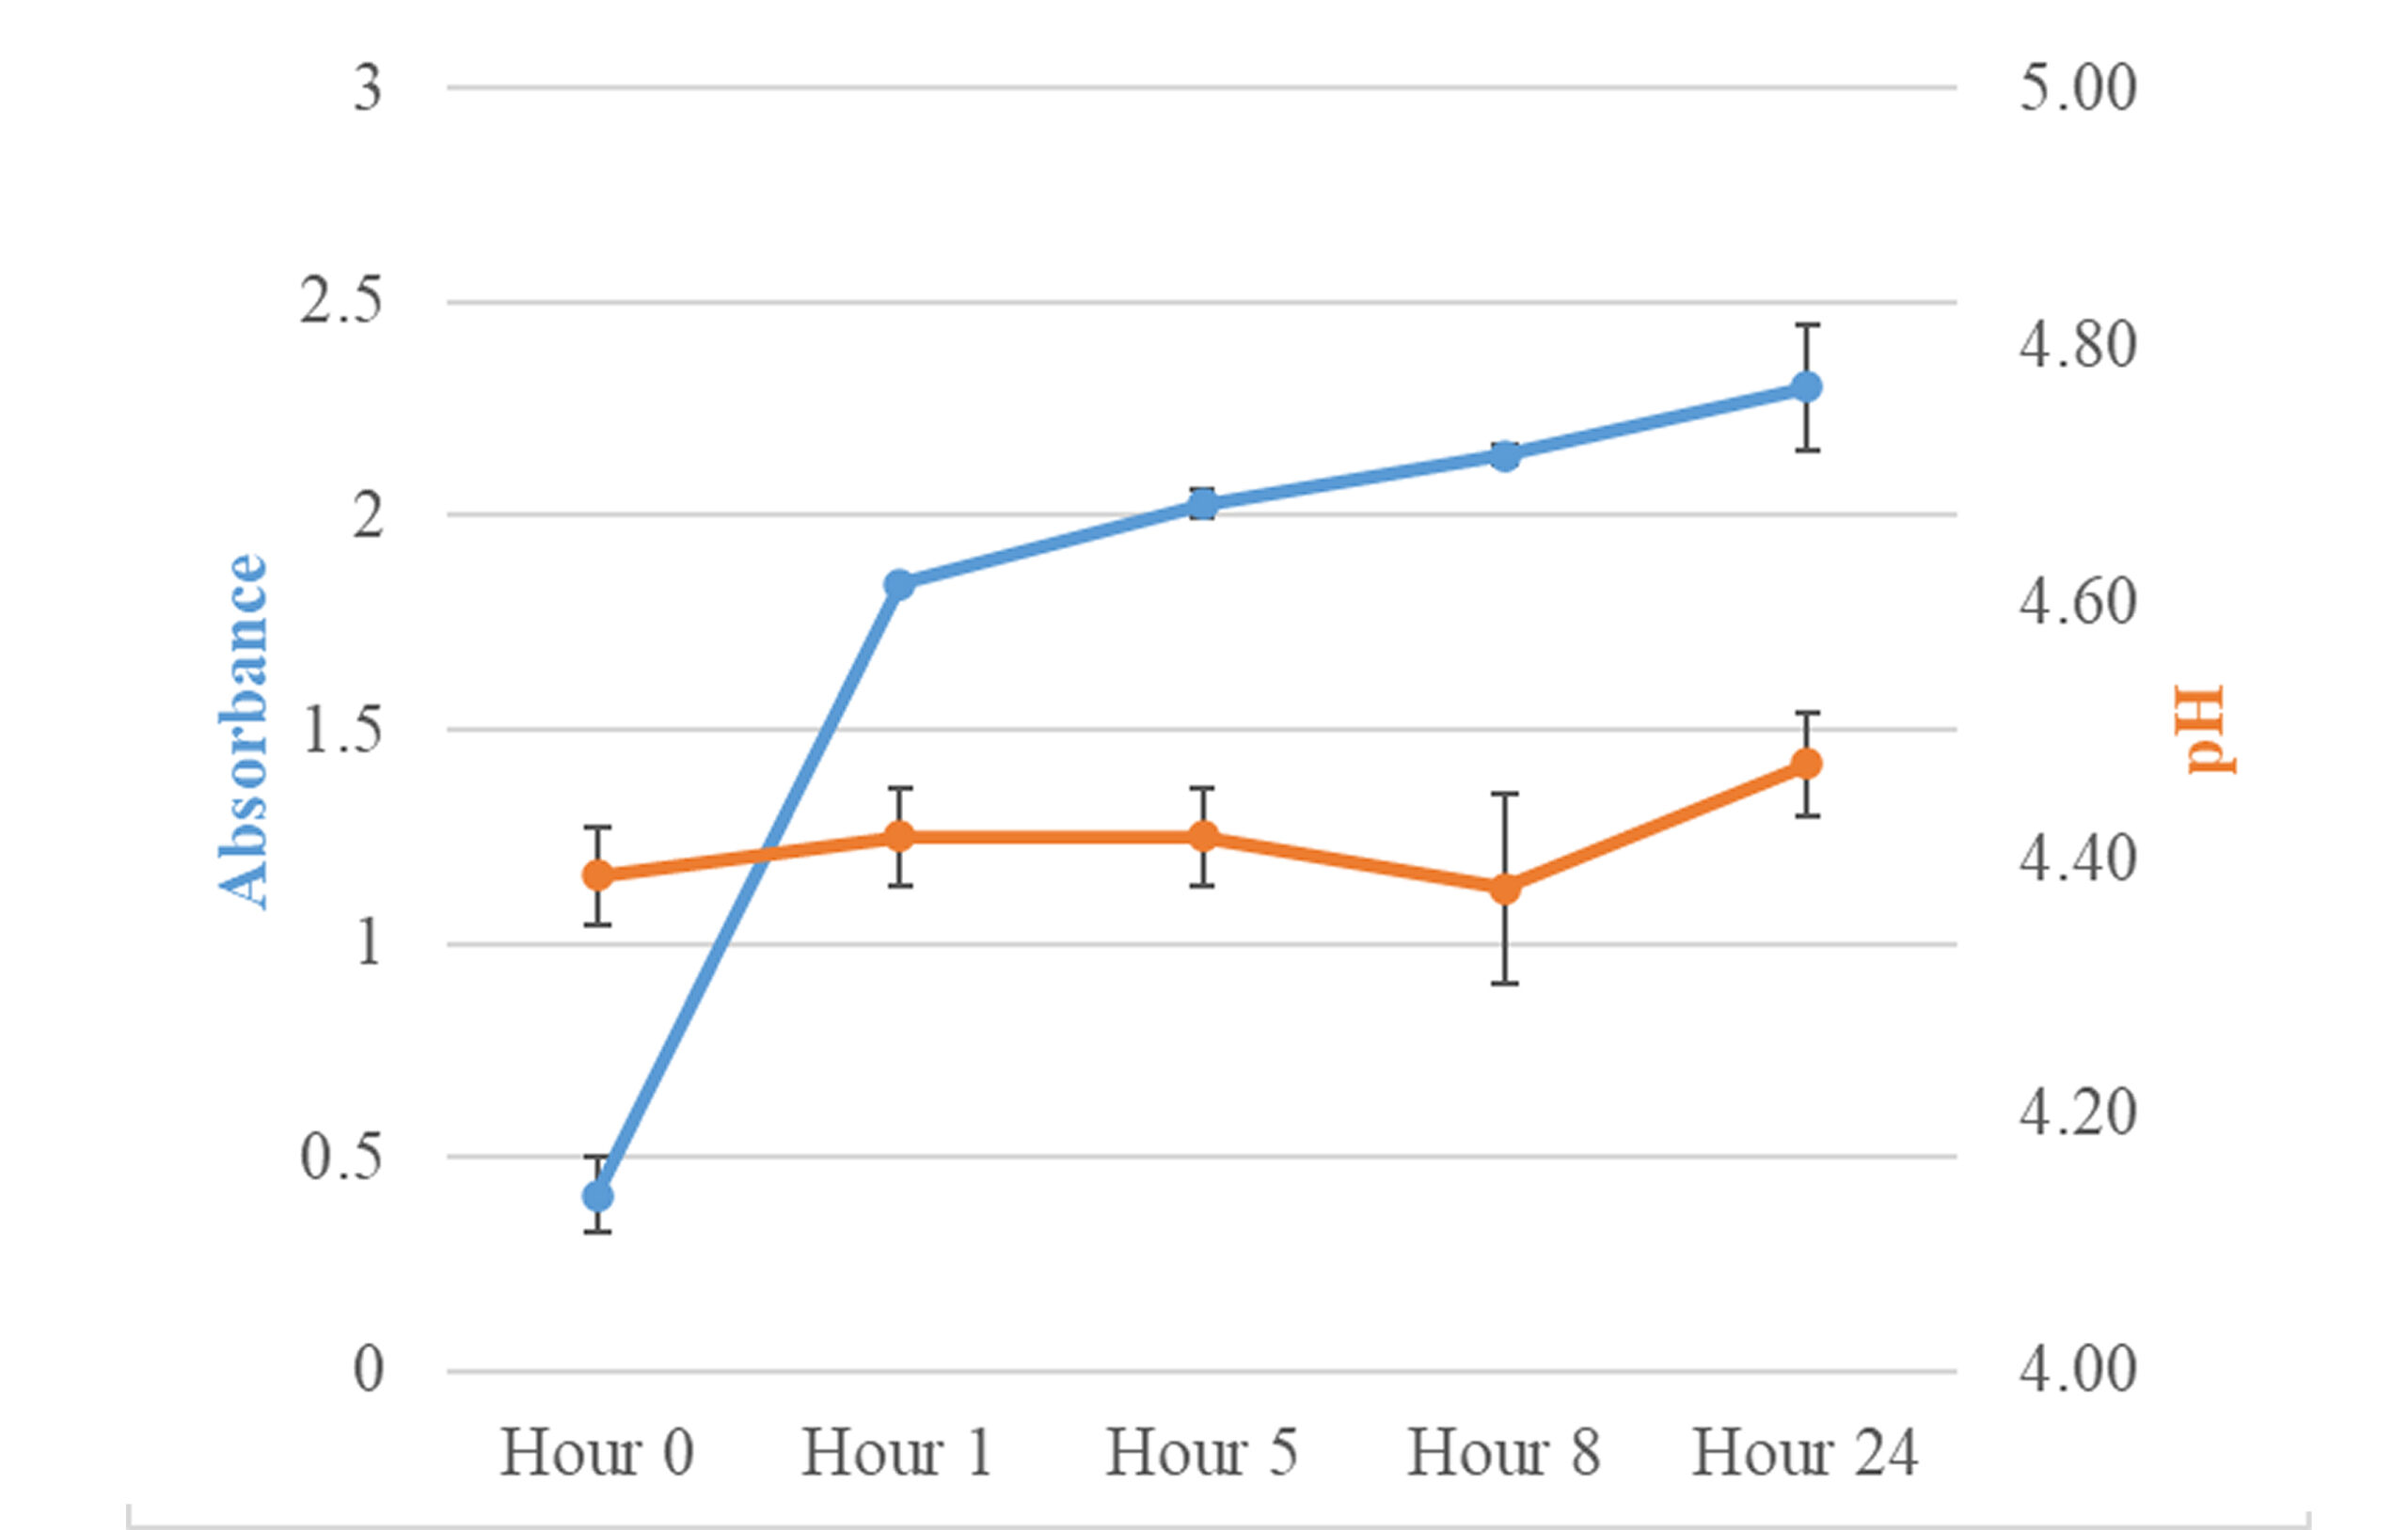

Pharmaceutical | Nov 13, 2025

In-Vitro Physical Compatibility of Intravenous Doxycycline Hyclate and Acyclovir Sodium

Introduction: The determination of physical compatibility of intravenous (IV) medications is crucial when multiple agents are co-administered to ensure patient...Read More